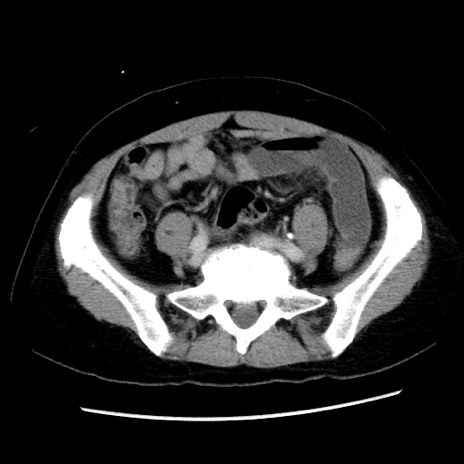

症例10(横断像)

【症例】 50歳代女性

【主訴】 腹痛

【現病歴】前日生レバーを食べた。今朝に排便あり。 昼前に突然発症の腹痛を生じ、当院救急外来を受診した。

【身体所見】 意識清明、腹部:平坦、軟、下腹部やや左を中心に圧痛・反跳痛あり、筋性防御あり

【データ】WBC 7800、CRP 0.07